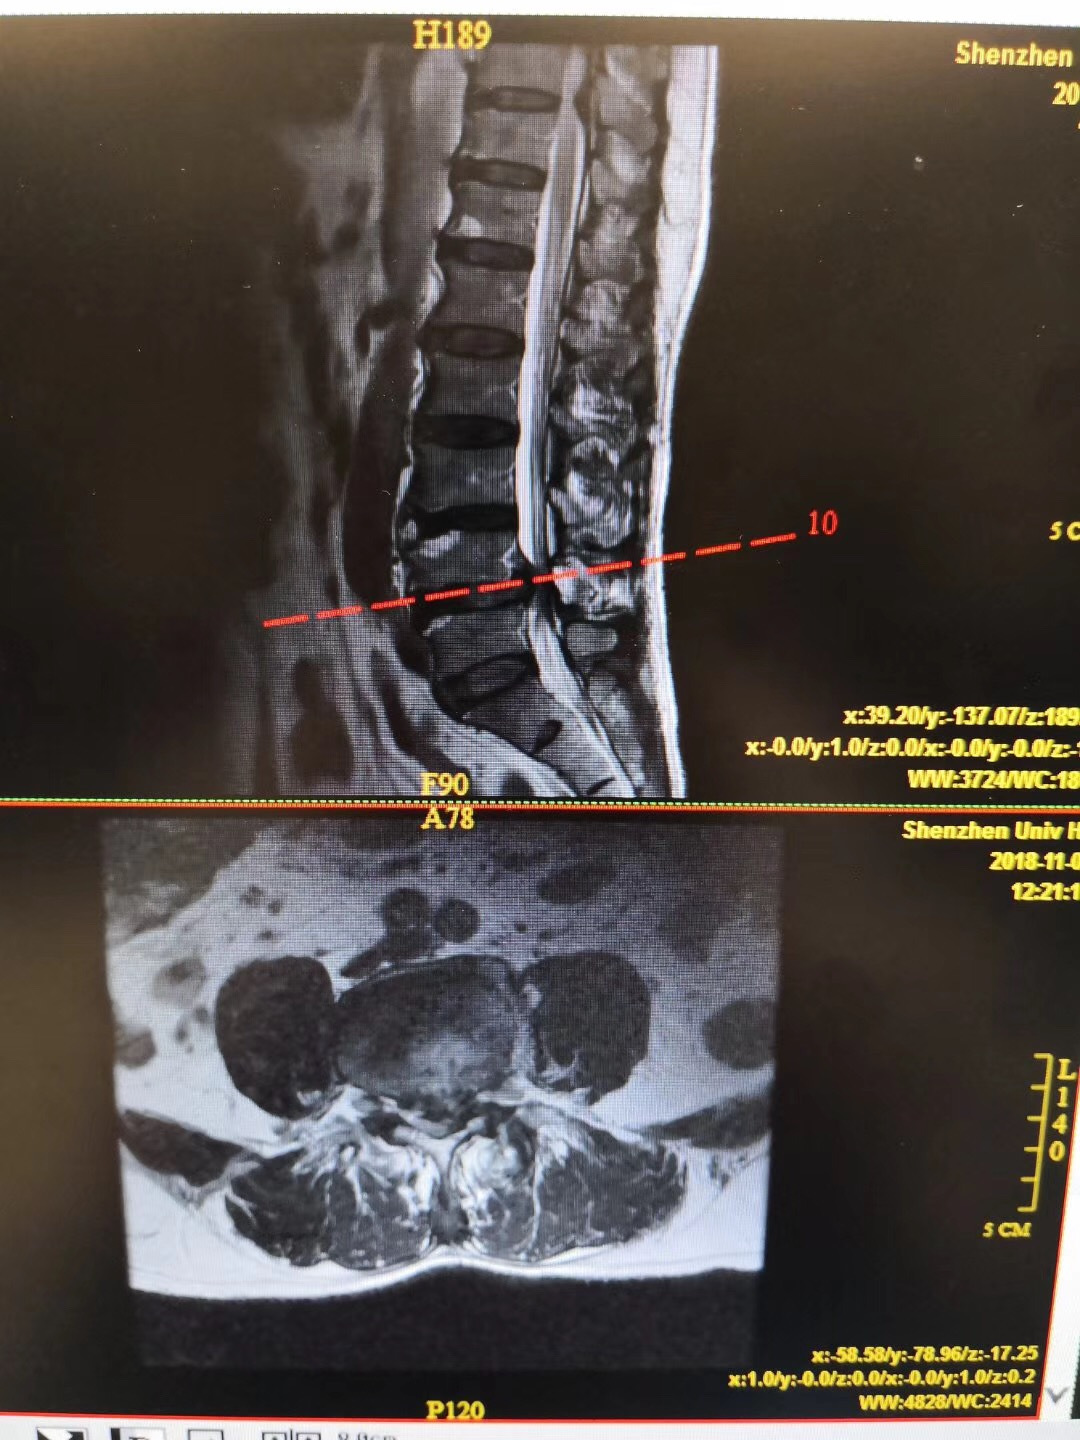

症状:双下肢麻痛伴间歇性跛行1年,行走100米即出现双下肢麻痛,严重影响生活。

诊断:腰椎间盘突出伴椎管狭窄症(L4/5节段),腰椎不稳定(L4/5节段),予施行“后路腰椎管减压固定融合术”治疗。